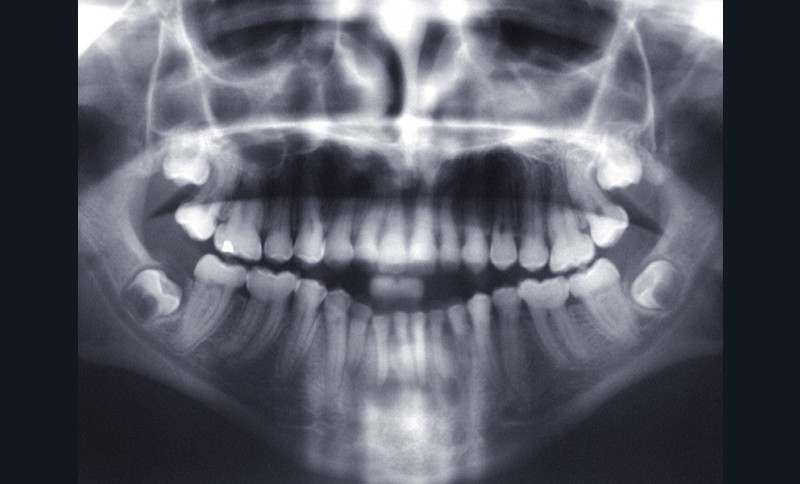

Teinte opalescente grise à jaune ambrée, couronnes globuleuses, calcifications intra-pulpaires, racines fines et courtes, attrition précoce, nécrose aseptique… Ces anomalies cliniques et radiographiques décrivent le tableau de la dentinogenèse imparfaite (DI) isolée de type 2. Cette anomalie génétique à transmission autosomique dominante est liée à un défaut de DSPP, gène de la sialophosphoprotéine dentinaire [1, 2]. Des anomalies dentinaires similaires résultent également de mutations de ce gène. Les avancées en recherche génétique tendent à réunir ces pathologies sous une même étiologie.

Un diagnostic précoce est primordial, car il existe aussi une forme associée à une anomalie osseuse, l’ostéogenèse imparfaite. Le chirurgien-dentiste est donc au premier plan pour dépister ces anomalies et limiter dès le plus jeune âge leurs conséquences infectieuses, fonctionnelles et esthétiques.